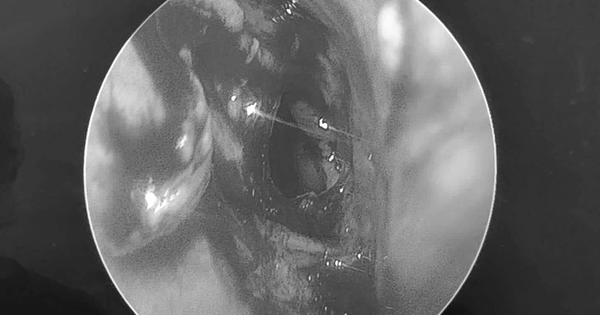

Người đàn ông xuất hiện tình trạng khó ở chịu mũi, sụp mi, mất thị lực hoàn toàn mắt bên trái, đau đầu dữ dội đến mức không chịu nổi liền đến viện.